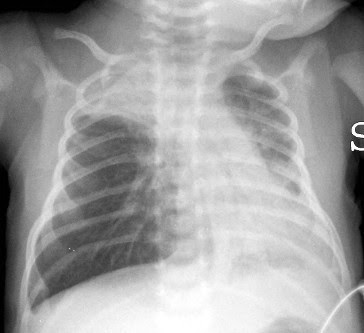

| Radiografía de los pulmones de un niño afectado por bronquiolitis. |

El nuevo anticuerpo monoclonal nirsemivab ha mostrado una efectividad de al menos el 70 % en prevenir la hospitalización de niños por culpa de la infección respiratoria por Virus Respiratorio Sincitial (VRS) en hospitales españoles. Estos son los resultados de un primer estudio de efectividad en entorno real del nuevo fármaco que ha capitaneado el departamento de Investigación en Vacunas de Fisabio-Salud Pública de la Comunitat Valenciana y que ha involucrado a 28 investigadores, nueves hospitales de tres autonomías (Valencia, Murcia y Castilla y León) y que ha contado con el soporte y la financiación del Instituto de Salud Carlos III vía fondos europeos Next Generation.